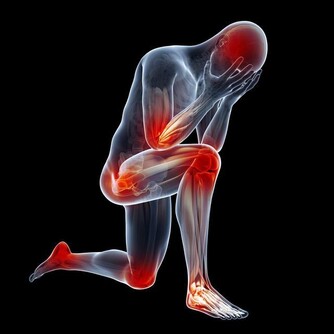

有人說,肝臟是沉默的器官,其實,它也會發出一些求救信號。